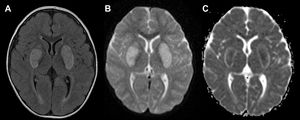

Niño de dos años y un mes acudió con varios días de fiebre, vómitos, irritabilidad y debilidad progresiva en las extremidades. A su llegada se encontraba somnoliento (escala de coma de Glasgow [GCS] E3 V3 M5) y hemodinámicamente estable. La analítica fue anodina, mientras que la prueba de antígenos respiratorios fue positiva para adenovirus. La tomografía computarizada (TC) cerebral sin contraste mostró hipodensidades simétricas bilaterales en los ganglios basales (fig. 1). El paciente fue ingresado en la unidad de cuidados intensivos por deterioro progresivo del nivel de conciencia. Los resultados del análisis del líquido cefalorraquídeo fueron anodinos, y los cultivos bacterianos y virales, negativos. Se administraron inmunoglobulina intravenosa, bolos de corticoides, manitol y cuidados de soporte. Posteriormente, en la resonancia magnética (RM) se observó restricción simétrica de la difusión en los ganglios basales (fig. 2), compatible con encefalopatía necrosante aguda de la infancia. El estudio metabólico descartó errores innatos del metabolismo. El paciente recibió el alta clínicamente estable, con alteración del lenguaje y labilidad emocional residuales.

A)RM en corte axial en secuencia T2 FLAIR que muestra hiperintensidades simétricas bilaterales en los ganglios basales. B)Difusión restringida en imagen ponderada en difusión (DWI). C)El mapa ADC (coeficiente de difusión aparente) correspondiente revela un núcleo hipointenso central rodeado por un borde hiperintenso, compatible con encefalopatía necrosante aguda de la infancia.

La encefalopatía necrosante aguda de la infancia es una encefalopatía fulminante asociada a infecciones, que presenta una mortalidad alta y secuelas importantes a largo plazo entre los supervivientes1. Las lesiones simétricas de los ganglios basales y el tálamo son signos radiológicos característicos y se aprecian mejor en la TC y la RM ponderada en difusión (DWI)2. Debido al mal pronóstico de esta enfermedad, aun con tratamiento, resulta esencial reconocer rápidamente estos hallazgos característicos en el ámbito de urgencias para poder intervenir a tiempo y maximizar la probabilidad de una evolución favorable3.